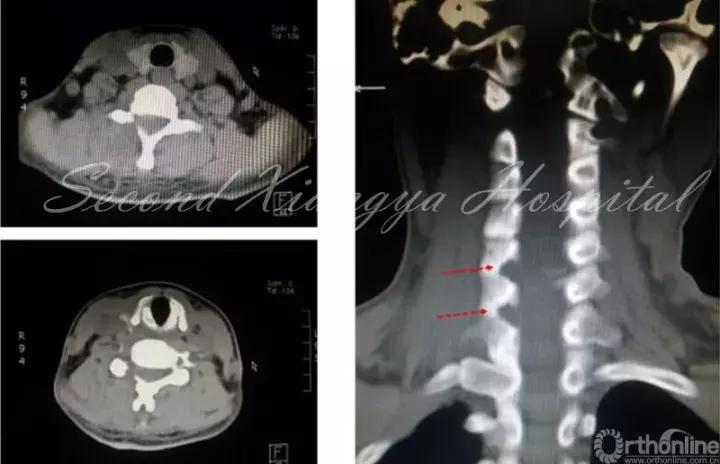

F,46岁,L4/5 LDH,外院行PETD后出现马尾综合征,转入中南大学湘雅二医院急诊行开放减压,术中发现髓核脱入到硬膜内。